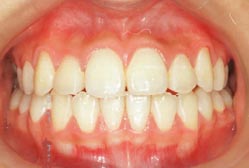

治療後